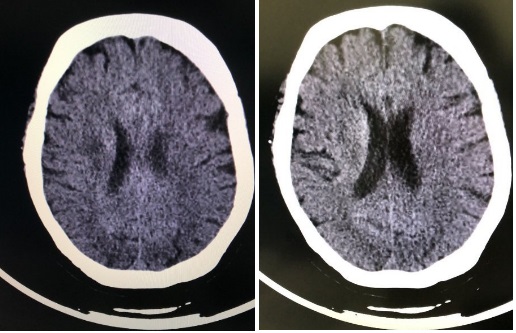

| 双肺小叶间隔增厚,双肺多发斑片影及磨玻璃影,双侧胸腔少量积液。心音增大,心包少量积液。肺动脉增粗 图 2 胸部CT |

该患者早期没有出现任何提示肺炎的临床表现,如咳嗽咳痰、咯血、胸闷胸痛等症状。如果我们没有对该患者进行胸部CT扫描,就会漏诊新型冠状病毒肺炎,根据患者肺部听诊、影像学表现及双下肢水肿体征考虑心源性因素所致肺水肿可能,而新型冠状病毒可能直接、间接感染心肌以及炎症风暴导致心力衰竭、心律失常等,不排除病毒感染间接导致肺水肿的可能,核酸检测结果当天回报阳性后将患者转往定点医院进一步治疗。

核酸检测临床诊断存在假阴性,且检测时间较长,部分患者血或咽拭子核酸检测虽阴性,但仍不能完全排除新冠肺炎病毒感染,而CT检测时间短,方便快捷,CT结果提示罹患COVID-19时,可以做到早发现,早诊断,早隔离,早治疗,对于急诊患者尤为适合,所以建议把CT作为早期筛查新冠肺炎的一个非常有效地手段。新冠肺炎患者的CT影像学表现为:早期呈多发的斑片状磨玻璃影及间质性改变,以肺外带明显;进展期表现为病灶增多、范围扩大,磨玻璃影与实变影或条索影共存;重症期表现为双肺弥漫性病变,少数呈"白肺"表现,以实变影为主,合并磨玻璃影,多伴条索影以及空气支气管征。胸腔积液或淋巴结肿大等症状少见。该患者的胸部CT示双肺小叶间隔增厚,双肺多发斑片影及磨玻璃影,双侧胸腔少量积液。心音增大,心包少量积液。肺动脉增粗,该患者血常规提示淋巴细胞减少,而新冠肺炎患者淋巴细胞减少较常见[9],根据患者的辅助检查提示新冠肺炎不能排除,因此我们立即给该患者进行了核酸检测,结果呈阳性,由此可见,在没有流行病学史、呼吸道症状、血象及炎症指标没有提示新冠肺炎是,胸部CT可作为新冠肺炎的一个有效初筛手段。